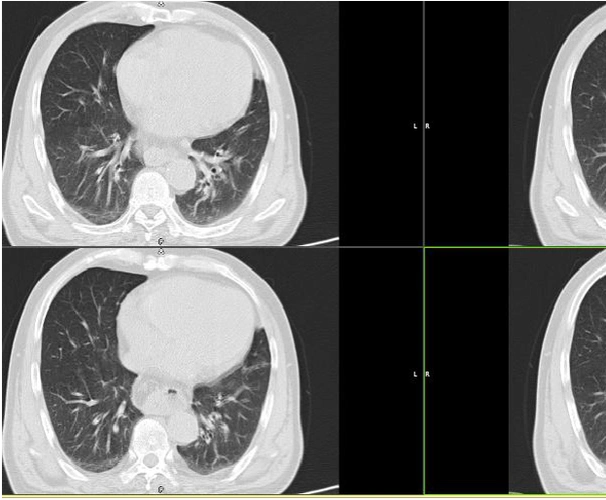

食管裂孔疝

食管裂孔疝ct表现